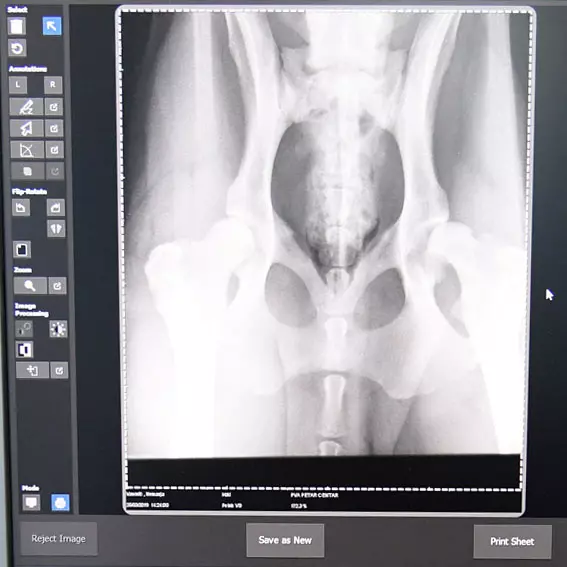

Radimo rendgensku dijagnostiku u maloj praksi i izdajemo sertifikate za kukove i laktove pasa.

Dodali bismo i to da se bavimo najpreciznijom rendgenskom dijagnostikom, jer pored velike stručnosti koju posedujemo, koristimo i najsavremeniju opremu.